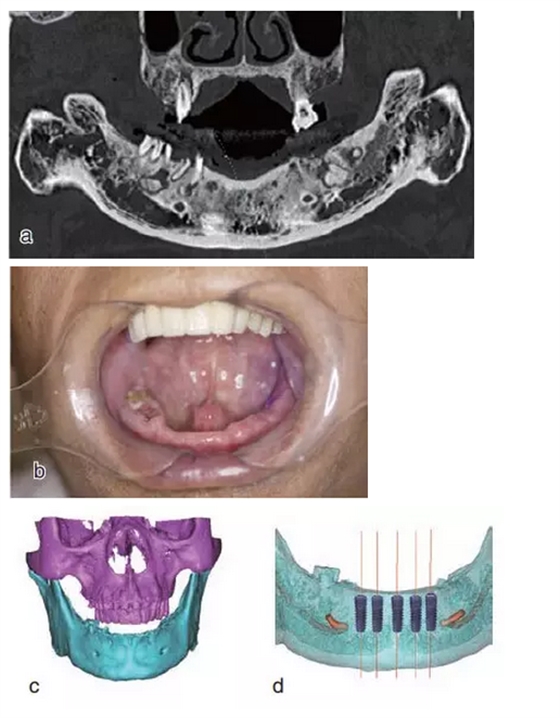

術(shù)前拍攝錐形束CT,進(jìn)行三維重建和種植方案規(guī)劃。從CT圖像中可以看出頜骨內(nèi)有骨島和殘根,為避免種植體植入骨島區(qū),考慮在兩側(cè)頦孔區(qū)種植4~5顆種植體,采用套筒冠進(jìn)行即刻修復(fù)。從重建的結(jié)果中可知前牙區(qū)牙槽嵴呈刀刃狀。種植方案為:對(duì)前牙區(qū)牙槽嵴進(jìn)行截骨修整,并在兩頦孔之間的區(qū)域內(nèi)植入5顆種植體。

圖15

種植方案的規(guī)劃:a.患者的CT圖像的截面圖,圈紅處為骨島;b.患者摘掉活動(dòng)義齒后的下頜;c.患者上下頜骨的CT三維重建;d.下頜骨截骨后模擬植入5顆種植體